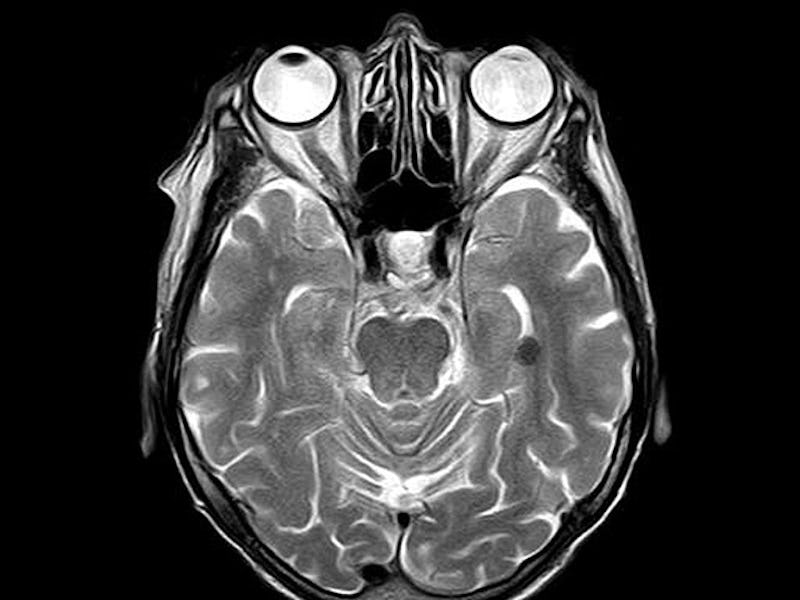

The team performed fMRI scans of 12 participants brains while they looked at a screen. Participants were told to look at a screen with two streams of text, and to switch paying attention from one to the other a few times a minute. Because the decisions made were voluntary, researchers could see what happens in the brain before a person decided to switch streams.

Before an individual decided to view a different stream, the fMRI picked up activity in two parts of the brain associated with attention, memory, and decision-making. Activity in these regions is starting earlier in comparison to previous studies where people are told to switch attention. This suggests that the medial frontal and lateral prefrontal cortexes are likely involved in processing decision-making.’